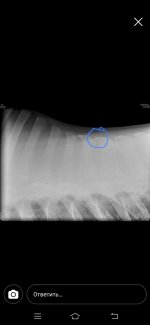

Нужна помощь. Лошадь 5 лет (6 лет будет в июне) обнаружили сегодня по ренгену спины серьезные проблемы.

По ренгену увидели что у лошади срослось костистые отростки ,образовалась хрящевая ткань. Как мне объяснили при ранней заездки лошади оказывалась не правильная работа принципе, был тяжелый всадник, не правильно подобраное седло. Из за этих факторов у лошади терлись друг об друга позвонки, произошло смещение + срастание. Как мне сказали теперь на лошади нельзя прыгать и нести верховные нагрузки. Только если будет хорошее седло +гель+меховушка ,и то если всадник не тяжелый и только (шаг, рысь, галопом в небольшом потвренмени количеству). В чем суть вопроса кто то может посоветовать подкормки или что то подобное

Как мне сказали это ничем не исправить уже...но можно что нибудь давать для поддержания формы или колоть (а вот что не сказали т.к. Врачи не специализировался именно на этом) есть ли тут ветеринары? Позже могу прикрепить снимки (когда скинут мне их на почту) спасибо всем заранее

По ренгену увидели что у лошади срослось костистые отростки ,образовалась хрящевая ткань. Как мне объяснили при ранней заездки лошади оказывалась не правильная работа принципе, был тяжелый всадник, не правильно подобраное седло. Из за этих факторов у лошади терлись друг об друга позвонки, произошло смещение + срастание. Как мне сказали теперь на лошади нельзя прыгать и нести верховные нагрузки. Только если будет хорошее седло +гель+меховушка ,и то если всадник не тяжелый и только (шаг, рысь, галопом в небольшом потвренмени количеству). В чем суть вопроса кто то может посоветовать подкормки или что то подобное

Как мне сказали это ничем не исправить уже...но можно что нибудь давать для поддержания формы или колоть (а вот что не сказали т.к. Врачи не специализировался именно на этом) есть ли тут ветеринары? Позже могу прикрепить снимки (когда скинут мне их на почту) спасибо всем заранее